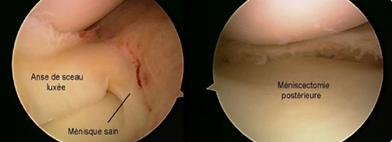

- Les lésions isolées (sur genou stable), siègent le plus souvent sur le bord libre du ménisque. Il s'agit de fissures verticales, radiaires, qui ne cicatrisent pas et qui peuvent détacher un fragment plus ou moins étendu (languette, anse de seau), source de blocage. Ces lésions doivent être réséquées par méniscectomie partielle.

Figure 2 : résection à l'aide d'une pince coupante d’une lésion en anse de seau du ménisque interne en vue de haut et en vue arthroscopique

- Les lésions associées à une rupture récente du LCA, sont toujours périphériques à type de désinsertion ménisco-synoviale. Ces lésions situées en zone rouge ont un fort potentiel de cicatrisation spontanée. Elles pourront bénéficier dans le même temps que la réparation du LCA, d'une abstention thérapeutique si elles sont stables ou d’une réparation par suture si elles sont instables (voir plus loin).

Figure 3 : lésion périphérique de la corne postérieure du ménisque interne en vue IRM et en vue arthroscopique (le crochet teste la stabilité de la désinsertion)

Sur genou laxe, les lésions méniscales sont le plus souvent représentées par une désinsertion périphérique du segment postérieur du ménisque interne. Malgré leur potentiel de cicatrisation spontanée, elles doivent être diagnostiquées et traitées. L’arthroscopie permet d’évaluer la taille et la stabilité de la lésion. Le ménisque devra être suturé, si la désinsertion fait plus de 10 mm de large ou si le ménisque désinséré peut être mobilisé sous le cond yle (Figure 3). Dans le cas contraire, un simple avivement de la lésion suffit pour permettre la cicatrisation. Que la laxité soit récente ou ancienne, il est souhaitable de réaliser dans le même temps que la suture méniscale, une réparation du LCA car les chances de cicatrisation sont de 90%.